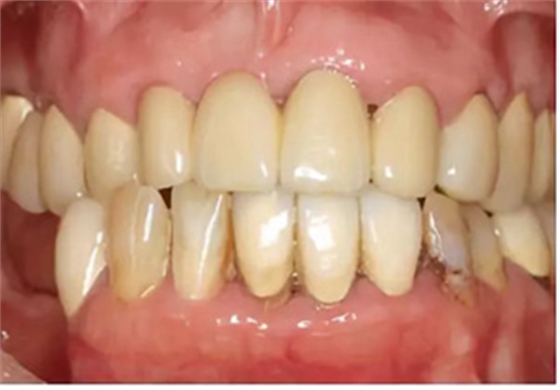

上頜義齒修復(fù)

在2014 年6 月6 日至2014 年11 月24 日期間,為患者做了上頜修復(fù)。由于14 和16 號牙齒的繼發(fā)齲已波及到現(xiàn)有的牙膠充填,所以為這兩顆牙齒做了根管再治療。24 號牙齒在其他醫(yī)生處進(jìn)行了根管治療。為了修復(fù)缺失的15 號牙齒,制作了16 至14 號牙齒的全瓷固定橋;13 號牙齒用全瓷單冠修復(fù);為了修復(fù)缺失的11 號牙齒,用12、21 和22 號牙齒做為基牙,同樣行全瓷固定橋修復(fù)。其余的牙齒用全瓷單冠修復(fù)。然后用長期臨時(shí)義齒修復(fù)下頜。